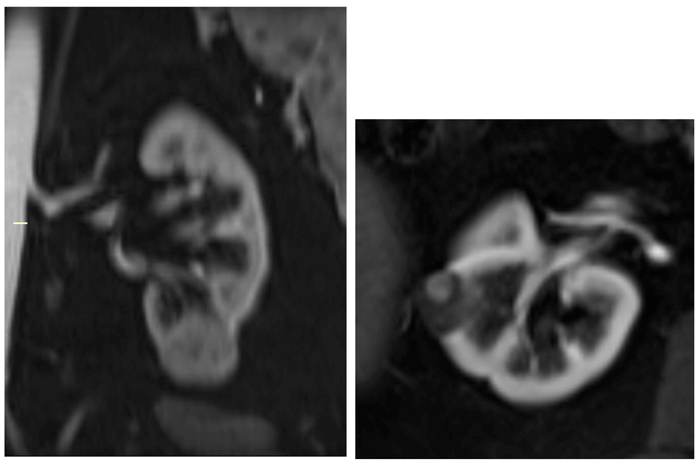

Figure 1: Incidental right indeterminate renal lesion on T2 weighted prostate MRI (left).

Subsequent focused ultrasound demonstrates a well circumscribed anechoic lesion consistent with a benign cyst (right).